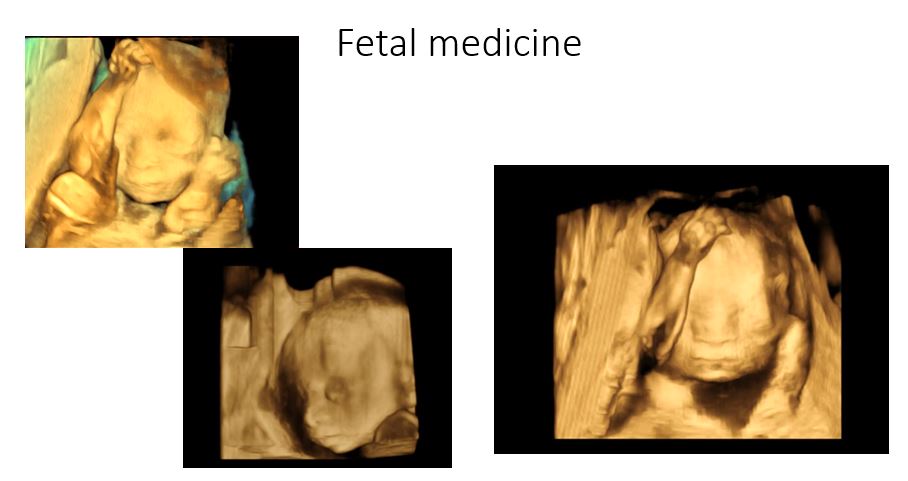

Fetal medicine:

- Routine and advanced fetal USG – TIFFA , growth scans, doppler, fetal ECHO

- Fetal interventions: Amniocentesis, Chorionic villous sampling, Fetal umbilical cord blood sampling, Fetal blood transfusion